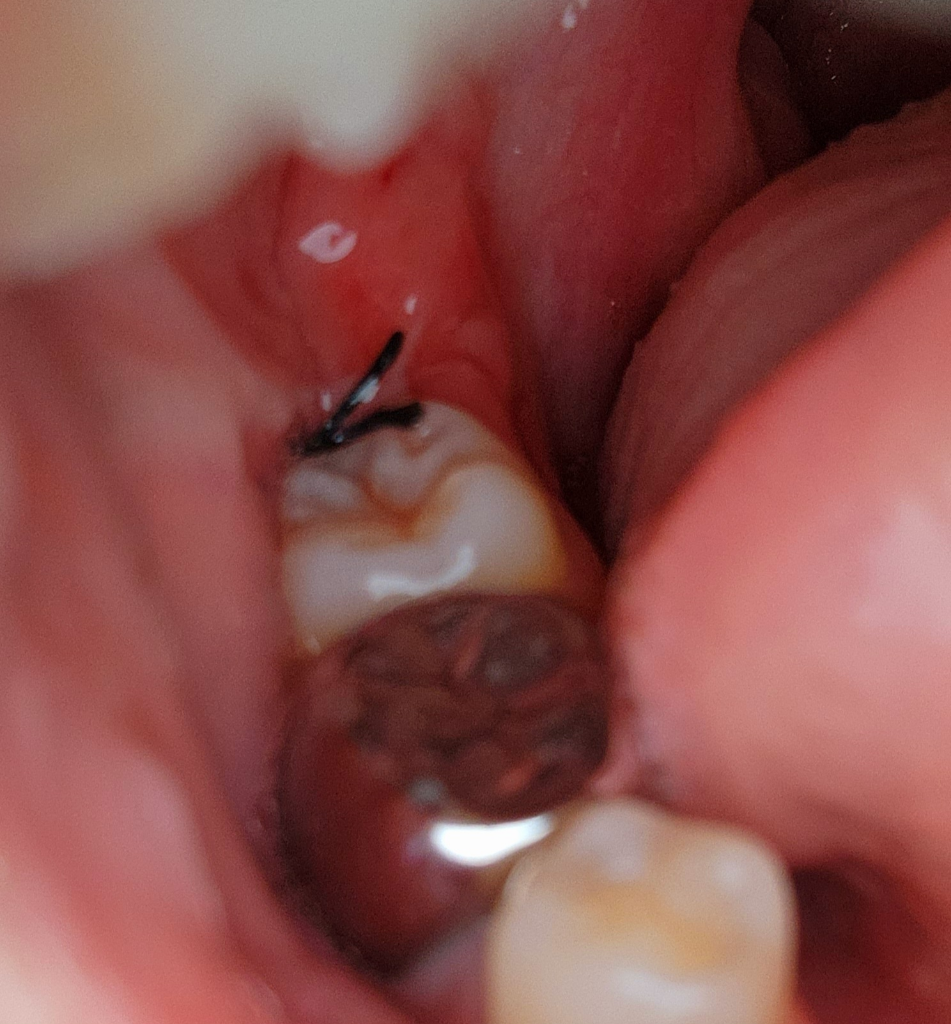

사랑니 실 봉합이 끊어진 건가요?

오늘 사랑니를 발치했는데

봉합이 끊어지거나 풀린건지 잘 모르겠어요

실의 가장 긴 부분 두 끝이 허공에서 달랑거리고 있어서 혹시나 끊어진건가 싶네요.

전문가가 보시기엔 어떠신가요? 재봉합 하러 가야 할까요?

3~4일 지난거면 걱정 안 할 텐데 오늘 발치한 거라 조금 걱정되네요

• 1번 째 사진

발치하고 나서는 잇몸이 부엇을때 실밥으로 꼬메기 때문에 붓기가 가라 앉으면 저렇게 보일수 있습니다. 문제가 잇는건 아니니 너무 걱정하지마세요.

사진으로 봤을 경우에는 봉합이 풀어지거나 한 것으로 보이지는 않습니다.

하지만 실밥이 걸리적거리고 난다면 치과에서 확인을 하고 제거를 하는 것이 좋습니다 실밥이 잡아당겨지고 나면 잇몸에 상처가 생길 수 있기 때문입니다.

풀리진 않은 것 같습니다 두가닥이 삐져나온 건 매듭이지어진 이후로 약간 길게 남겨둔 것입니다